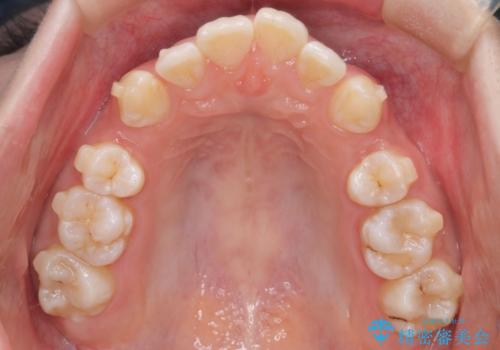

重度の歯のがたつきを、目立たない矯正と抜歯で根本改善

- 前歯から奥歯にかけて歯の重なりが激しい歯のがたつき(重度叢生)を主訴にご来院されました。精密検査の結果、歯が並ぶスペースが大幅に不足しており、歯並びを整え、口元を美しく引っ込めるためには、スペースの確保が必要と診断しました。そこで、上下左右の第一小臼歯(4番目の歯)を計4本抜歯し、そのスペースを利用して歯並び全体を整える抜歯矯正の治療計画を立案。装置には、透明で目立たないインビザラインを採用し、審美性と治療効果の両立を目指しました。

今回の治療では、重度の叢生を改善するため、まず計画通り上下左右4本の小臼歯を抜歯し、歯を並べるための十分なスペースを確保しました。装置には透明で取り外し可能なインビザラインを使用。抜歯によってできたスペースを最大限に活用し、マウスピースを定期的に交換しながら、デコボコを解消しつつ、前歯を効果的に後退させました。

治療の結果、長年の悩みであった重度の歯のがたつきが解消され、口元の突出感も改善。機能的にも安定し、審美的にも美しい、理想的な歯並びを獲得していただけました。